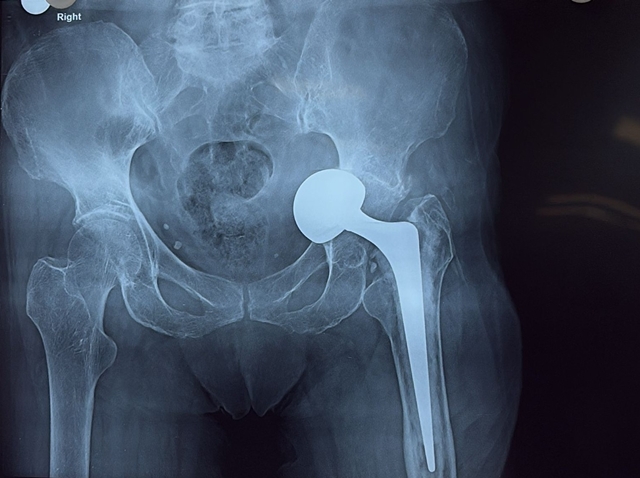

The elderly patient had been experiencing severe pain in her left hip and difficulty bearing weight due to complications from a previously implanted hip prosthesis. Medical evaluation revealed that the implant had gradually migrated inward into the pelvic cavity, a rare and technically challenging condition known as intrapelvic protrusion of the prosthesis.

Given the complexity of the case and the patient’s advanced age, the orthopaedic team undertook a detailed clinical assessment and multidisciplinary planning before proceeding with surgery. The surgical team performed a revision total hip replacement using an antiprotrusio cage, a specialised implant designed to reconstruct the hip socket and provide strong structural support when bone strength is compromised.